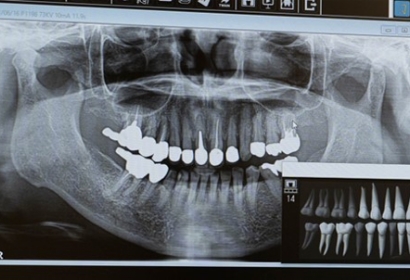

インプラント治療において、口腔内の状態が把握できていないと神経や血管を傷つけてしまう可能性があります。そのため、術前にはCT撮影や模型での噛み合わせ分析などを行っています。

様々な資料や歯科用デジタルレントゲンに加えて、3DCT画像による手術部位の分析を徹底することで、より安心・安全にインプラント治療を行うことができます。